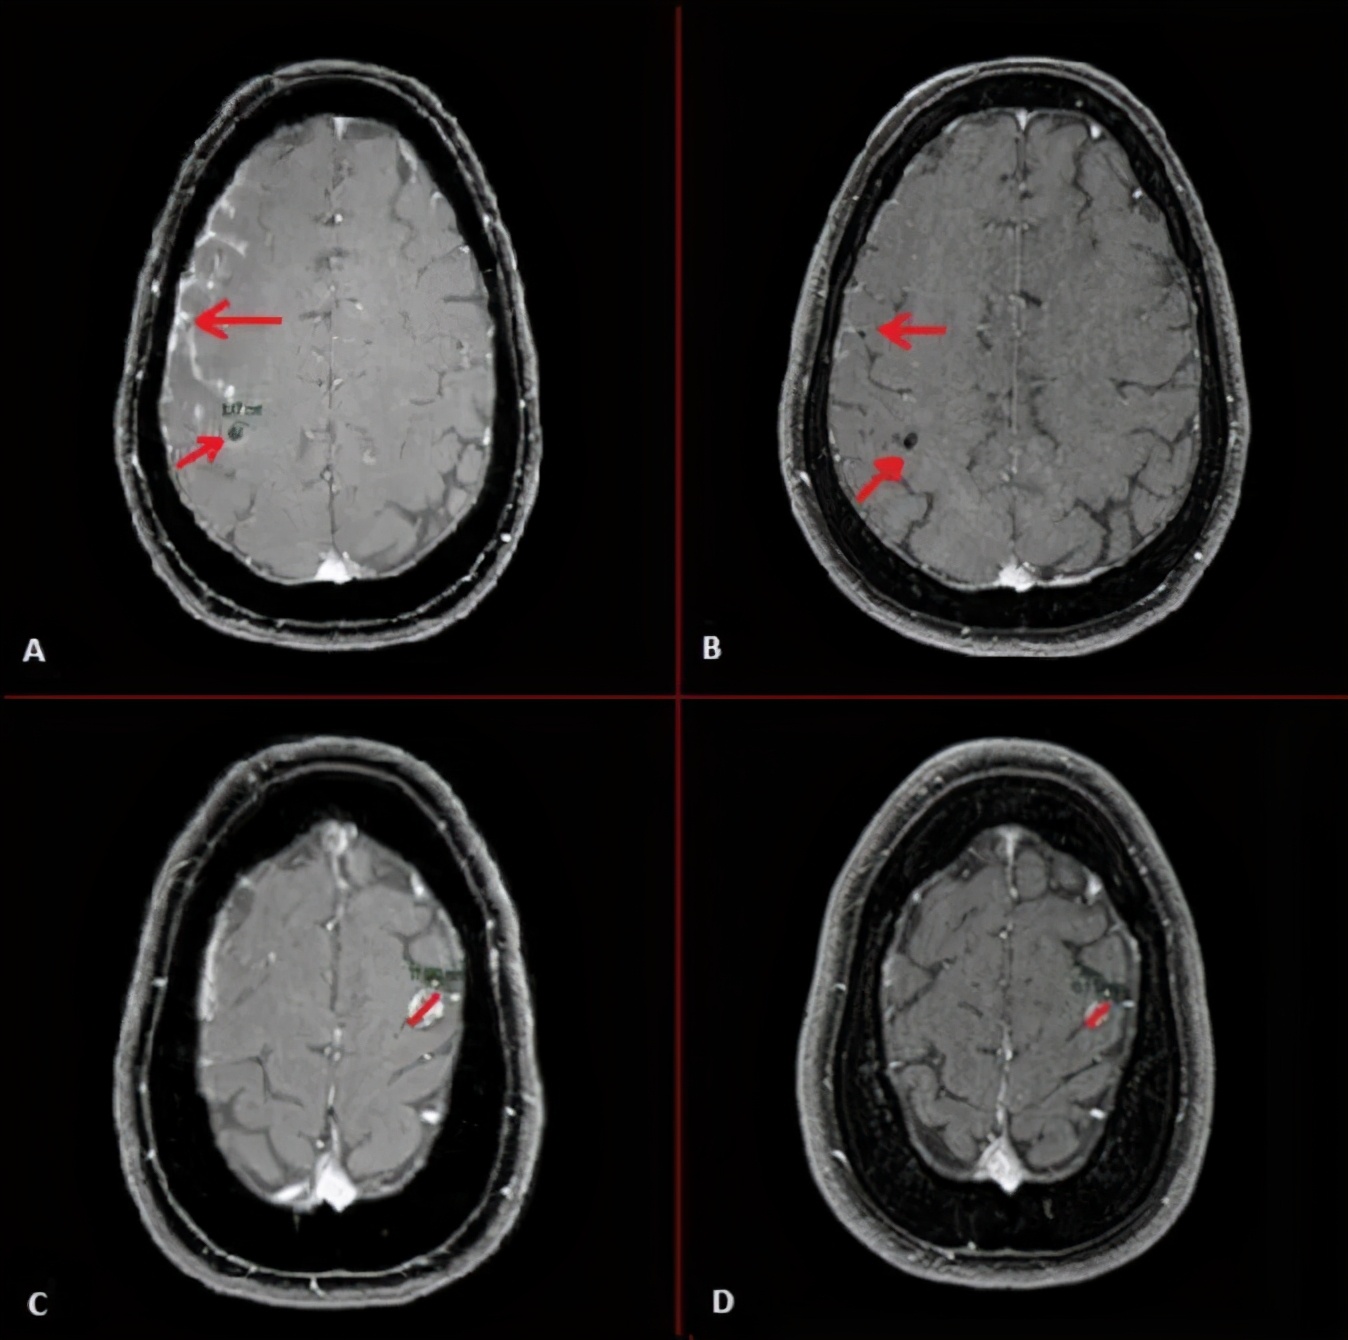

下面是M女士的MRI,A,C图显示在克唑替尼使用期间发生了多个颅内转移,B,D显示M女士接受劳拉替尼治疗一周后,颅内转移灶迅速消退,肿瘤标记物迅速下降。